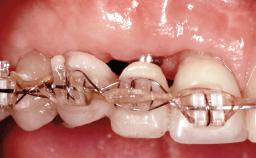

A 38-year-old woman presented with an esthetically unacceptable fixed partial denture replacing teeth 11, 21, 22. She had lost these teeth due to trauma when she was a child. The patient was not in pain but very concerned based on her previous experience that dental treatments had never satisfied her esthetic expectations. She was in good general health and reported no regular medications. No periodontal disease was noted despite the fact that the buccal flange of the prosthesis impeded cleaning of the tooth abutments. The patient did not smoke and complied with home maintenance requirements, as evidenced by her good oral hygiene status.